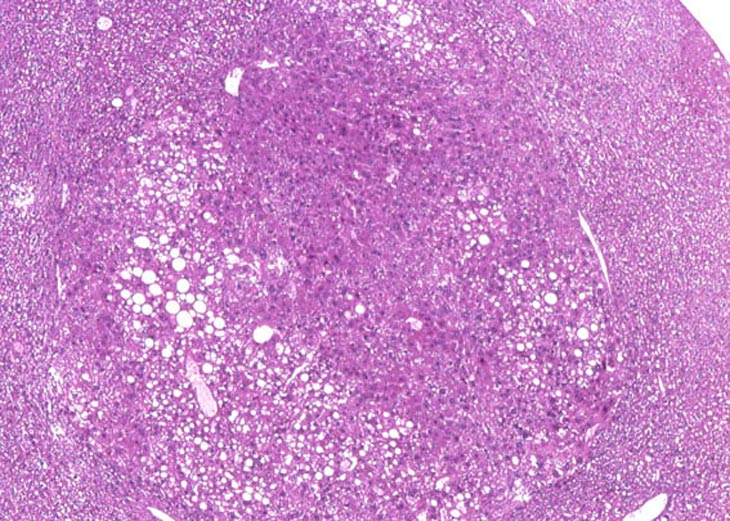

A large and a small clear cell focus of cellular alteration. Clear cell foci are characterized by relatively clear cytoplasm or cytoplasm with just a hint of very pale eosinophilic staining and wispy strands of cytoplasm making the cytoplasmic vacuoles have an indistinct border. Unlike vacuolated foci, many cells within a clear cell focus have a centrally located nucleus. The clear space is produced when stored glycogen is dissolved out during fixation in aqueous fixatives.

This clear cell focus actually has light pink staining of the cytoplasm.